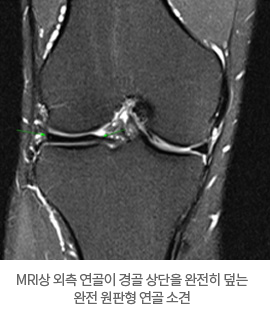

원판형 반월상 연골에는 세 종류가 있습니다. 원판형 연골이 경골상단의 일부를 덮는 불완전 원판형 연골, 연골이 경골 상단을 완전히 덮는 완전 원판형 연골, 전반월대퇴인대가 없는 Wrisberg 연골로 분류됩니다.

X-선 검사에서 바깥쪽의 대퇴골과 경골이 만나는 지점의 관절 간격이 넓어져 있는 것이 관찰되는 경우도 있습니다. MRI 검사는 무릎 관절의 연부 조직의 상세한 이미지를 얻을 수 있고 원판형 반월상 연골의 검사에 있어 가장 확실한 검사 방법입니다.

MRI상 외측 연골이 경골 상단을 완전히 덮는 완전 원판형 연골 소견